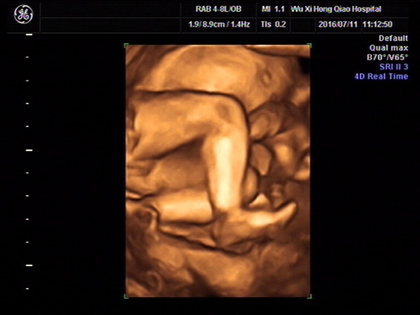

网上流传着四维彩超的报告上如果是有三条线就是女孩,而如果没有三条就是男孩,那么四维女宝宝三条线特征图片长什么样呢,四维男宝也有三条线吗?

其实网上流传着的这种说法并没有依据,原因是网上说的三条线是指女孩生殖器上的线,但是四维彩超上面一般医生是不会显示出完整的生殖器的,还有就是,四维彩超的三条线是无法看出男女性别的,这三条线代表的是脊柱线,还有就是通过三条线来看男女性别的方式误差也是比较大的。

四维彩超其实是实时的三维,是有一个立体成像的过程,因为胎儿是团抱式的,胎儿一部分会被遮挡,所以四维应该会更准确一些,但是不是绝对的。实际在B超进行胎儿性别鉴定时,有可能男孩生殖器被遮挡导致误认为是女孩,因此还是要找专业的医生来看才能下结论。